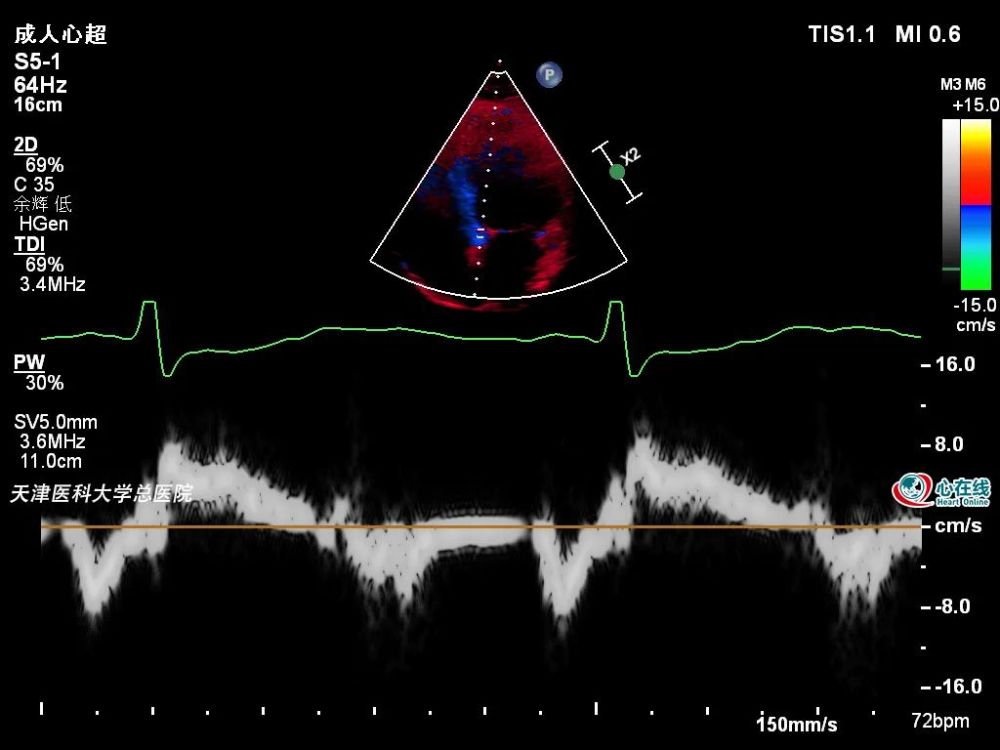

根据美国超声心动图学会/欧洲心血管影像协会测量左心室舒张功能流程

图2‐1‐235 缩窄性心包炎患者,二尖瓣血流频谱e峰 明显升高,e/a增大

图2‐1‐233 缩窄性心包炎,心包钙化3﹒脉冲多普勒超声心动图 主要